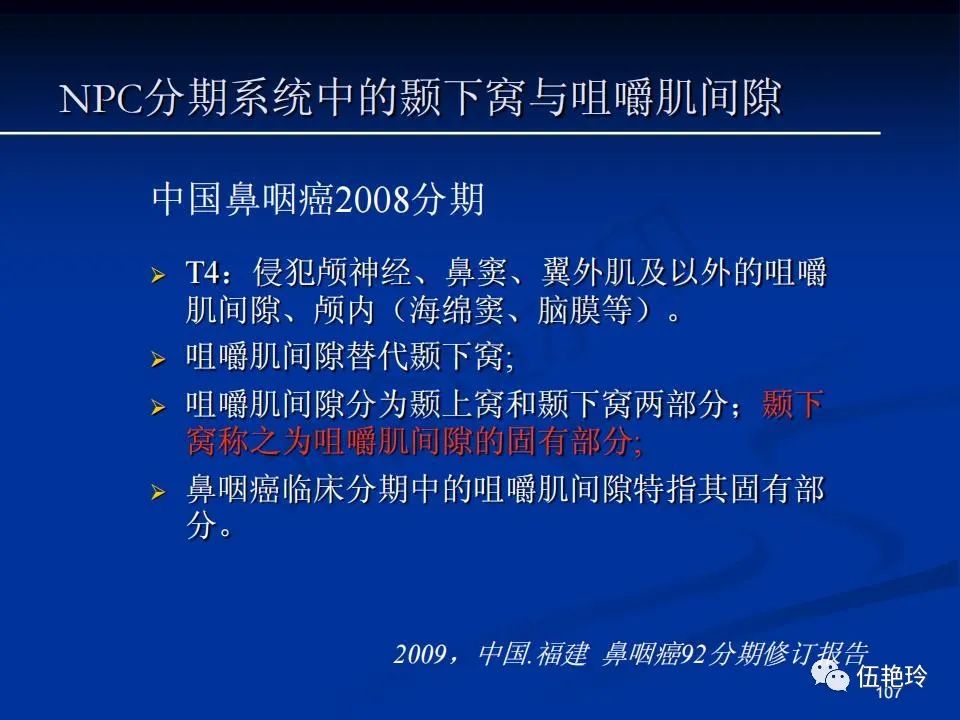

颞下窝与咀嚼肌间隙

2.31 向上颅内:①鼻咽顶壁→破裂孔(岩尖、斜坡)→蝶窦、海绵窦;②鼻咽顶壁→蝶骨基底部→蝶窦、海绵窦;③鼻咽侧壁→茎突前间隙→蝶骨大翼(卵圆孔)→海绵窦;④鼻咽侧壁→茎突前间隙→翼腭窝→ 颞下窝;⑤鼻咽前壁→鼻腔→翼突、翼腭窝→眶下裂→眶尖→海绵窦;⑥鼻咽前壁→鼻腔→上颌窦、筛窦;